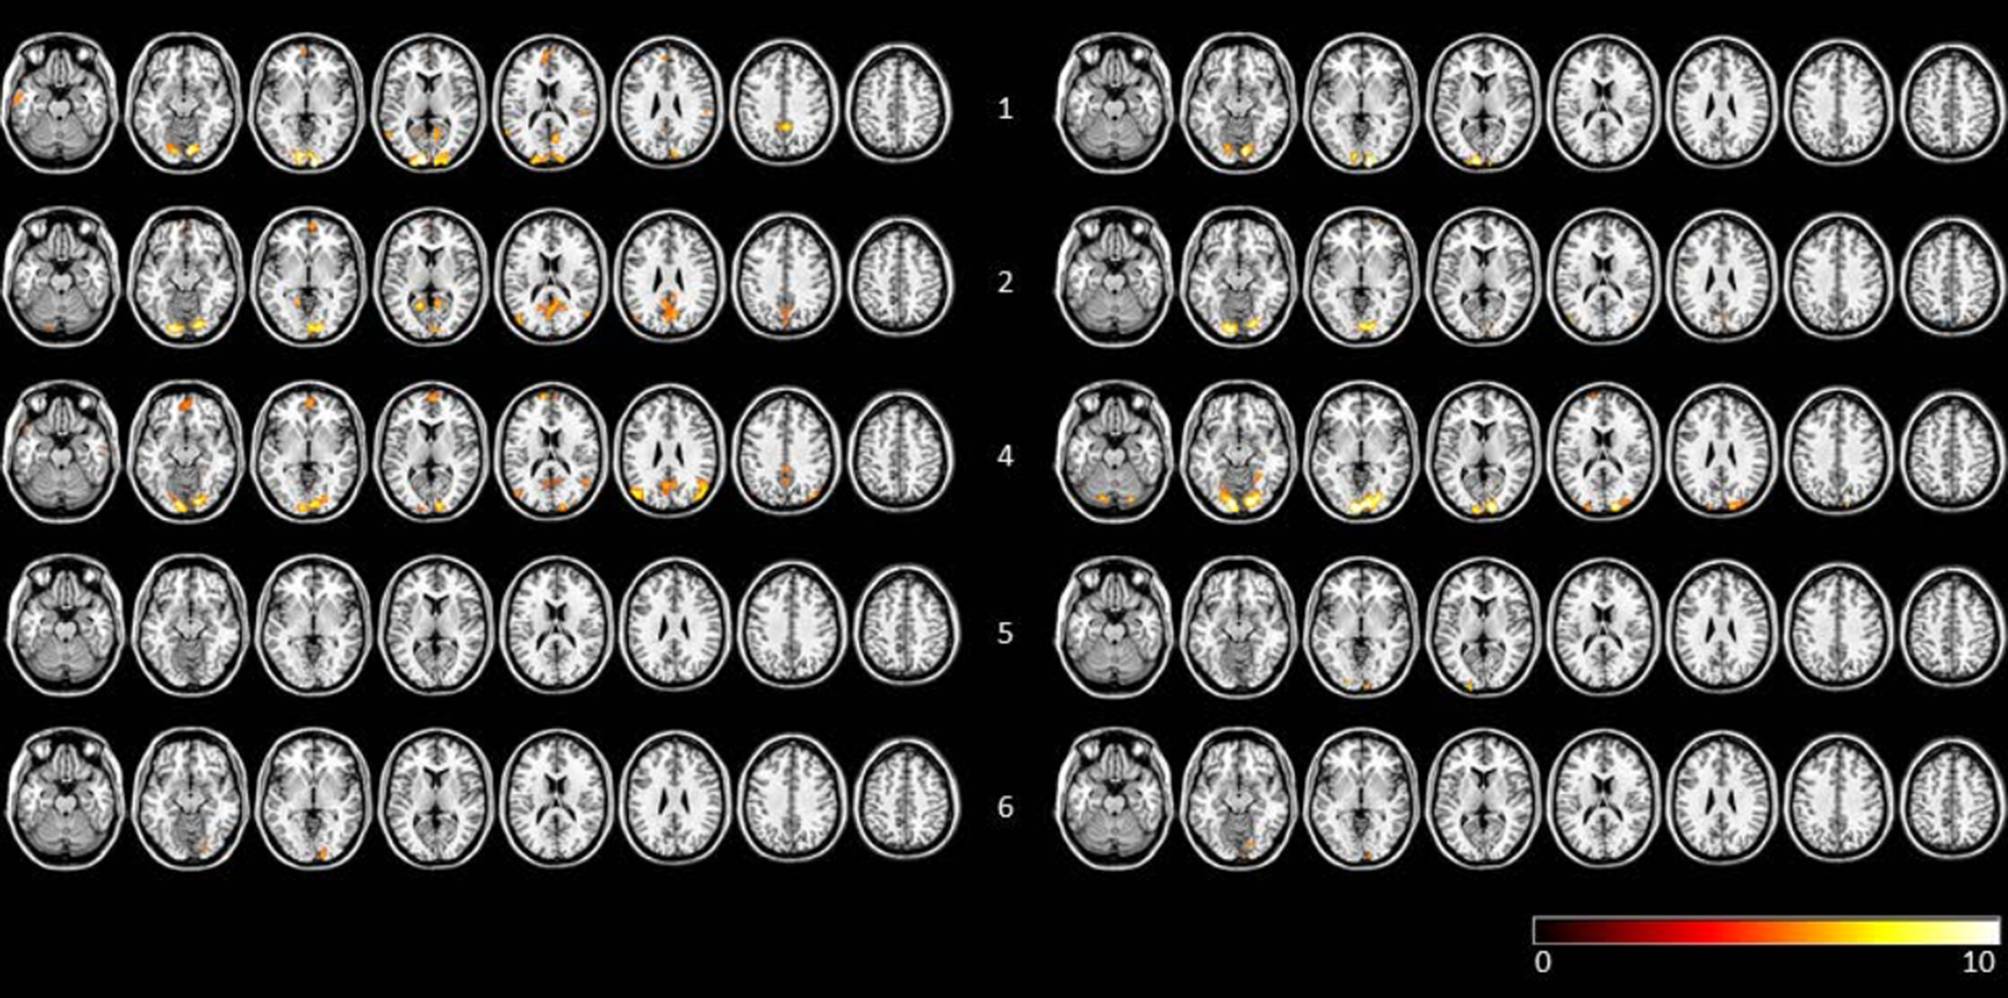

In 4 of the 6 AP + CR subjects the number of clusters increased, whereas in 4 out of the 5 AP subjects the number of clusters decreased (mean number of clusters: AP + CR = 5.53, SD 12.79, AP = −5.8, SD 6.9; see Table 1 for details). Individual activation maps for AP + CR subjects before and after therapy are shown in Fig. 1 and for AP subjects in Fig. 2.

Fig. 1

Visualization of FFX results of pretherapy and posttherapy n-back task runs for AP + CR subjects (FWE corrected, p < 0.005). Row labelling refers to subject number. To the left of the subject number individual scans before therapy are shown, to the right of the subject number the scans after therapy are shown. Data are visualized on a standard template using MRIcron. AP+CR group subjects with atypical antipsychotics and cognitive remediation, FFX fixed effects analysis, FWE family-wise error